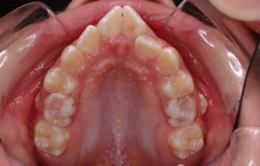

②歯と顎の大きさのバランス

・歯が顎に比べて大きい(逆に言うと顎が小さい)場合歯は凸凹に生えて叢生という状態になります。歯が生えてくる時、早く生えてきたものが場所を占領しますので、多くの場合最後に生えてくる上の犬歯は生える場所が無くなりいわゆる「八重歯」になってしまいます。

・逆に歯が顎に比べて小さい場合、もしくは歯が欠損していたり生えてこないままであったりすると、すきっ歯、空隙歯列弓歯という状態になります。